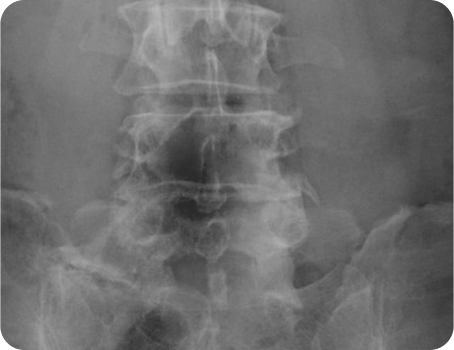

척추분리증

척추 사이가 좁아진 부위에 이상이 나타난 상태로 대부분 5번 허리뼈에 주로 발생합니다.

척추분리증이 있다고 해서 무조건 증상이 나타나는 것은 아니며, 허리를 뒤로 젖히거나 오래 걸을 때 통증을 호소합니다. 시간이 흐를수록 척추분리증이 발생한 부위가 불안정해지는데, 척추전방전위증으로 이어질 수 있기 때문에 주의가 필요합니다.

원인

• 선천적 척추 이상(사춘기~20대전후부터 통증 호소)

• 오랜 동안 충격에 노출된 허리

• 과격한 운동(축구, 체조, 레슬링, 다이빙, 무술)

• 장기간 바르지 못한 자세

• 척추의 퇴행성변화